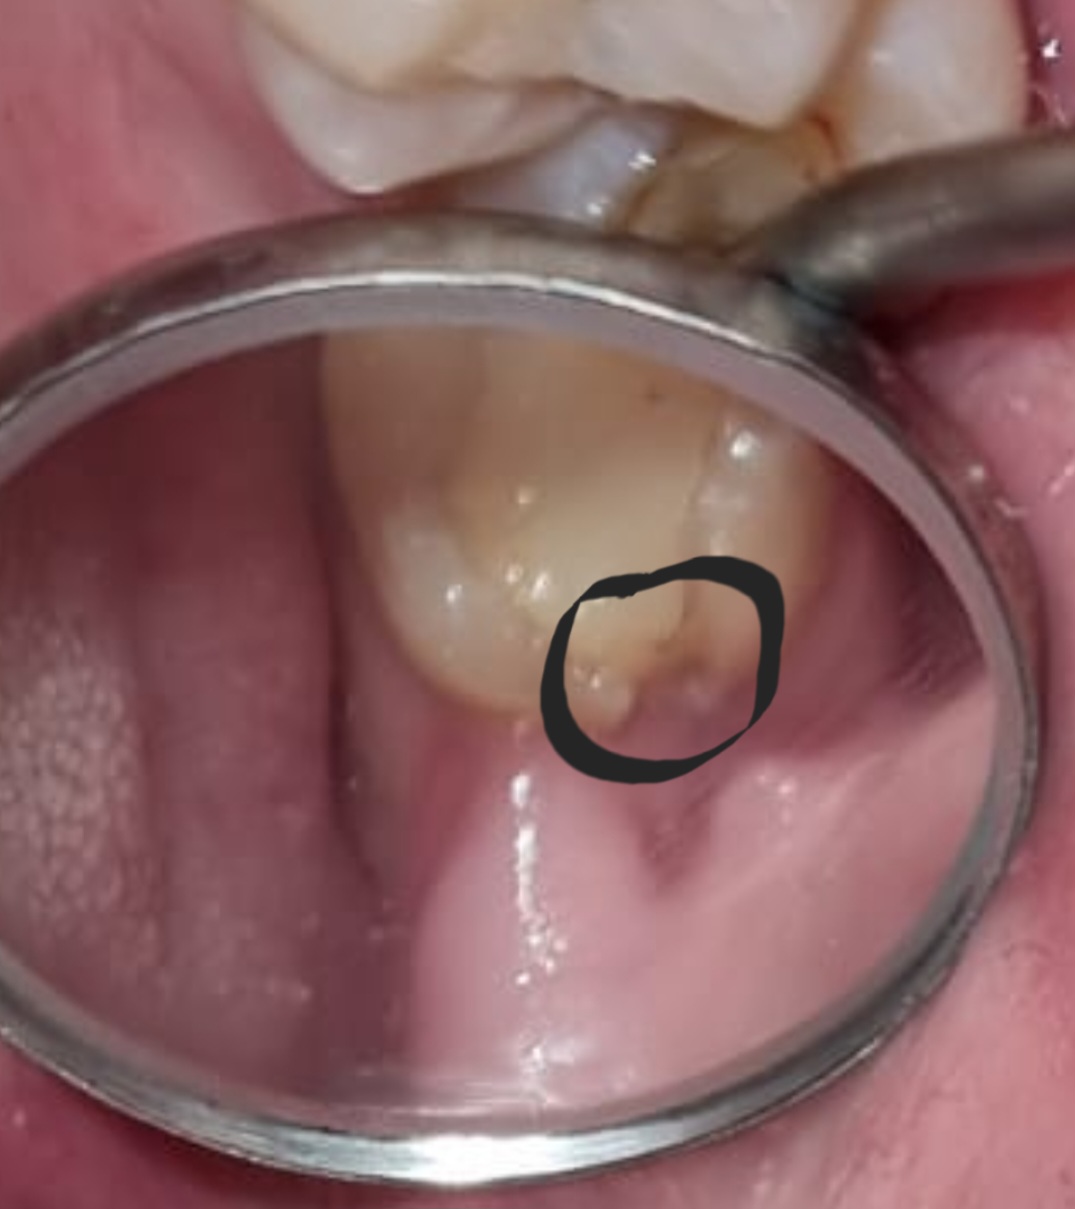

Er is een klein stukje van mijn laatste kies afgebroken. Ik ben nogal bang voor de tandarts. En vraag mij af hoe ze dit gaat herstellen. Moet er bijvoorbeeld geboord worden? Of kan dit best eens zonder pijn te hebben hersteld worden. Ik heb er geen last van doet ook geen pijn

Geen last betekent niet niets doen. Als de remmen v uw auto versleten zijn wacht u ook totdat u tegen een boom bent gereden alvorens de remmen te vervangen. Verdoven, restant vulling eruit boren, schoon maken en opnieuw vullen. Door de verdoving voelt u alleen dat wij bezig zijn maar geen pijn. Bent u ook bang als u uw haar, nagels knipt/laat knippen. Heb vertrouwen in de handen die u helpt.